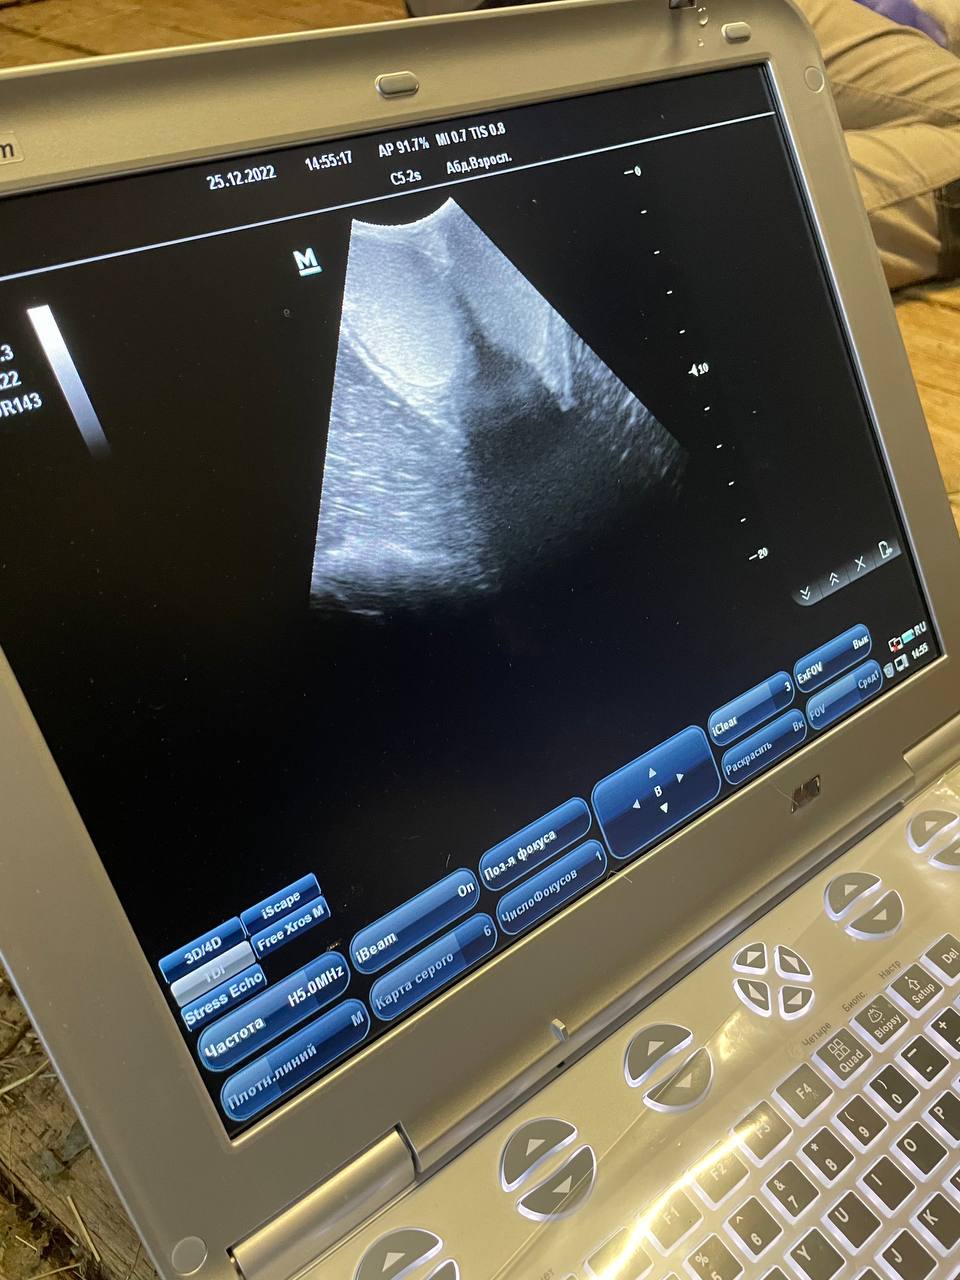

Спорим, вы не видели, как тапиру делают УЗИ?

В нашем зоопарке равнинный тапир добровольно соглашается на ветеринарные исследования. Всё дело в тренировках.